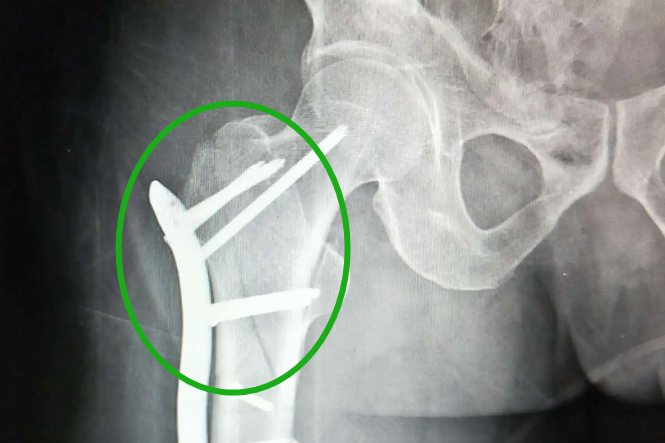

股骨转子间骨折:

转子间骨折的临床表现与股骨颈骨折相似,主要的鉴别的在于,转子间骨折的外旋畸形可以达到90°。同时可在CT或是X光片下观察到转子间的骨折线。